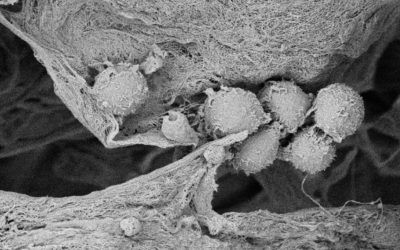

Cancer Stem Cells Embedded in Sanatela Matrix

When Sanatela researchers place a 6mm “disk-like” segment of the Matrix into a cell dish in the laboratory and then add patient leukemia cells, they immediately are drawn to, attach themselves and become embedded. Upon evaluation, these attached cells were found to have stem-cell properties. We believe other cancers will behave the same way. This process of seeding cell dishes with Matrix disks is clearly demonstrated in our video that can be found on the Sanatela website www.sanatelamedical.com